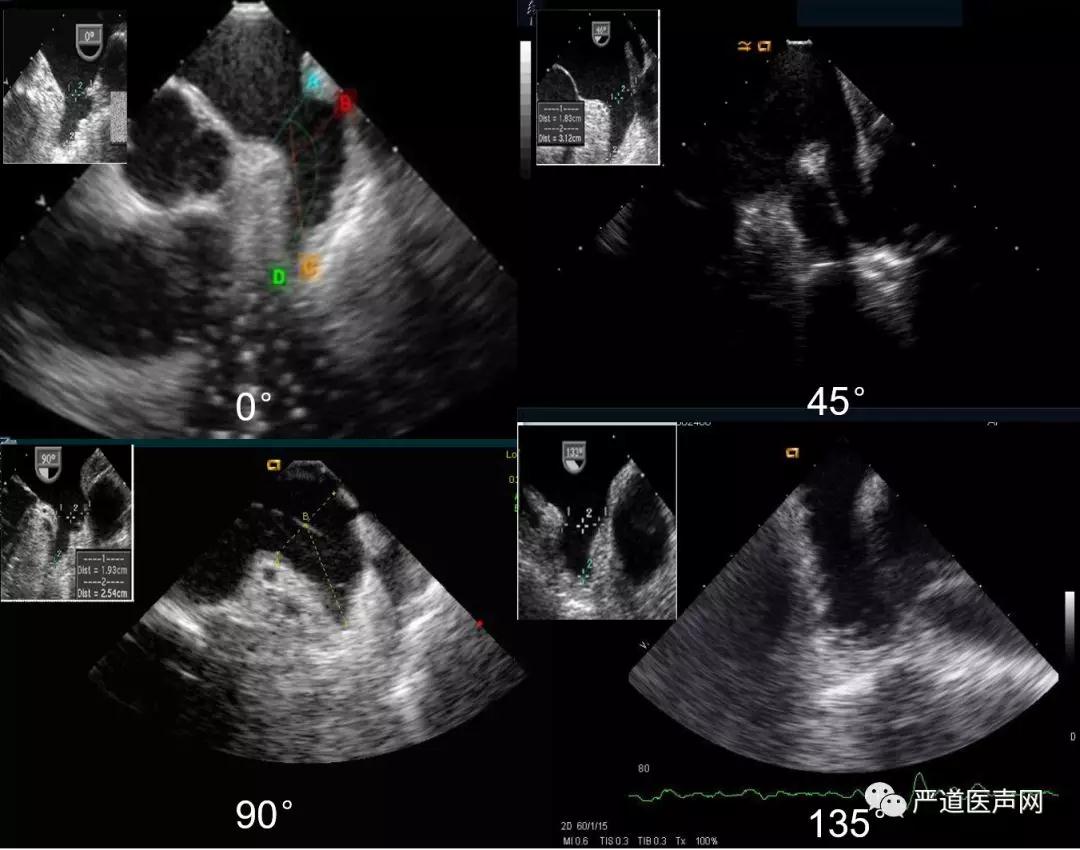

在TEE术前检查中,分别需要0°,45°,90°,135°的多角度评估,对应ICE,通常在左房中部(mid-LA),可以观察到左心耳短轴开口,此时相当于0-45°的TEE视野, 相对容易实现;当探头位于左房底部时,在此基础上倾斜180°,可观察到左心耳长轴开口,相当于90-135°的TEE视野,这里需要一定的经验积累和导管操作微调,具体主要操作介绍如下。

0°-探头置于mid-LA时,再推送1cm左右,邻近左上肺静脉口部偏后顶上区域,此时缓慢逆时针旋转直到可见主动脉短轴斜切面,此时左心耳开口;

45°-探头置于mid-LA时,可见二尖瓣的视野下,调节张力旋钮并轻微打P弯;

90°-也叫工作角度,当探头置于mid-LA并可见二尖瓣的视野下,缓慢推送在距离左上肺静脉口部1cm处适当调节张力旋钮并轻微打L弯;

135°-探头置于mid-LA时并可见二尖瓣的视野条件下,控制张力旋钮并打中度L弯。

图9 与TEE相匹配的ICE视野观察左心耳结构